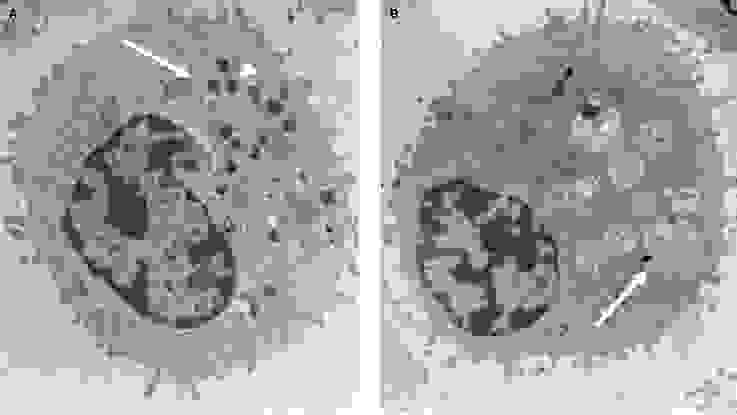

صورة مجهربة للخلايا التائية